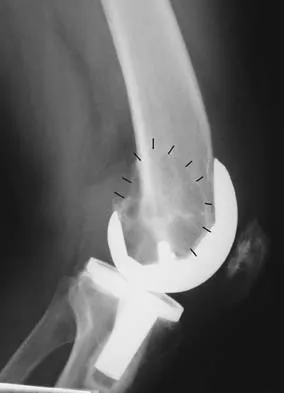

Question 13

Figure 43 shows the lateral radiograph of a patient who underwent anterior cruciate ligament reconstruction. Based on the tunnel placement shown in the radiograph, evaluation of postoperative knee range of motion will most likely show

Explanation

The radiograph shows the correct tibial tunnel and anterior femoral tunnel; therefore, range of motion will most likely show loss of flexion. Brown CH Jr, Carson EW: Revision anterior cruciate ligament surgery. Clin Sports Med 1999;18:109-171.